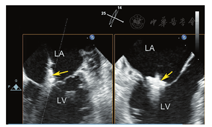

超声心动图在MR介入术中起着不可或缺的作用,下面以目前最为成熟的经导管二尖瓣夹合术MitralClip为例,阐述MR介入术中的超声评价。MitralClip是在TEE实时监测和引导下的操作,所有的导管操作由TEE监测和引导[16]。TEE首先引导房间隔穿刺,使得房间隔穿刺点距二尖瓣瓣环平面的高度3.5~4 cm(图11)。之后,TEE引导输送系统进入左心房并调弯、顶端垂直指向二尖瓣口。接着,TEE引导夹合器在二尖瓣上方定位,夹合器进入左心室,引导夹合器捕获和夹合瓣膜。夹合器捕获瓣膜位置,应该位于彩色多普勒显示反流束最大处。在整个手术过程中,两个超声切面非常重要,为手术的工作切面(X-plane双切面),包括三腔切面(左心室长轴切面)及二尖瓣交界处两腔切面(图12),前者可以显示二尖瓣A2、P2的位置,捕获瓣膜前二尖瓣夹合器应该在这个切面显示为"V"形,此时瓣夹合器臂与二尖瓣开放线垂直,分别位于A2、P2的位置,在该切面通过调整夹合器位置可使得夹合器更靠近前叶或后叶;后者显示P1,A2,P3,捕获瓣膜前二尖瓣夹合器在该平面应该为直线形,在该切面通过调整夹合器位置可使得夹合器更靠近内交界(3)或外交界(1)。另外一个工作切面为三维超声心动图的"二尖瓣外科视野",可以整体观察夹合器的位置、臂指向的方向(图13)。目前有限经验显示,经心尖二尖瓣夹合术(ValveClamp)术中超声指导和MitralClip总体上类似,但仍有部分差异,其超声规范尚在探索中。